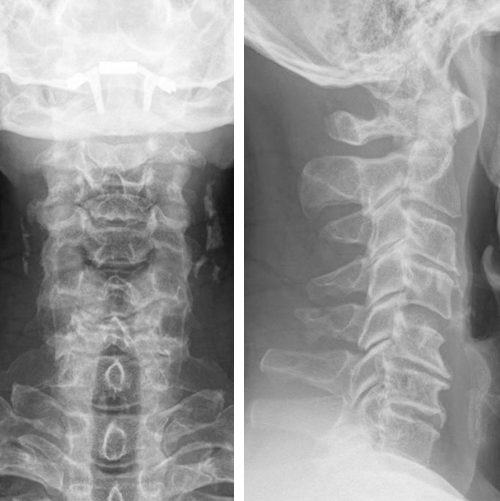

The radiograph indicated:

- Degenerative discs and spondylosis C3-4-5-6-7

- No translational instability on flexion-extension

- Loss of lordosis (Fig 4)